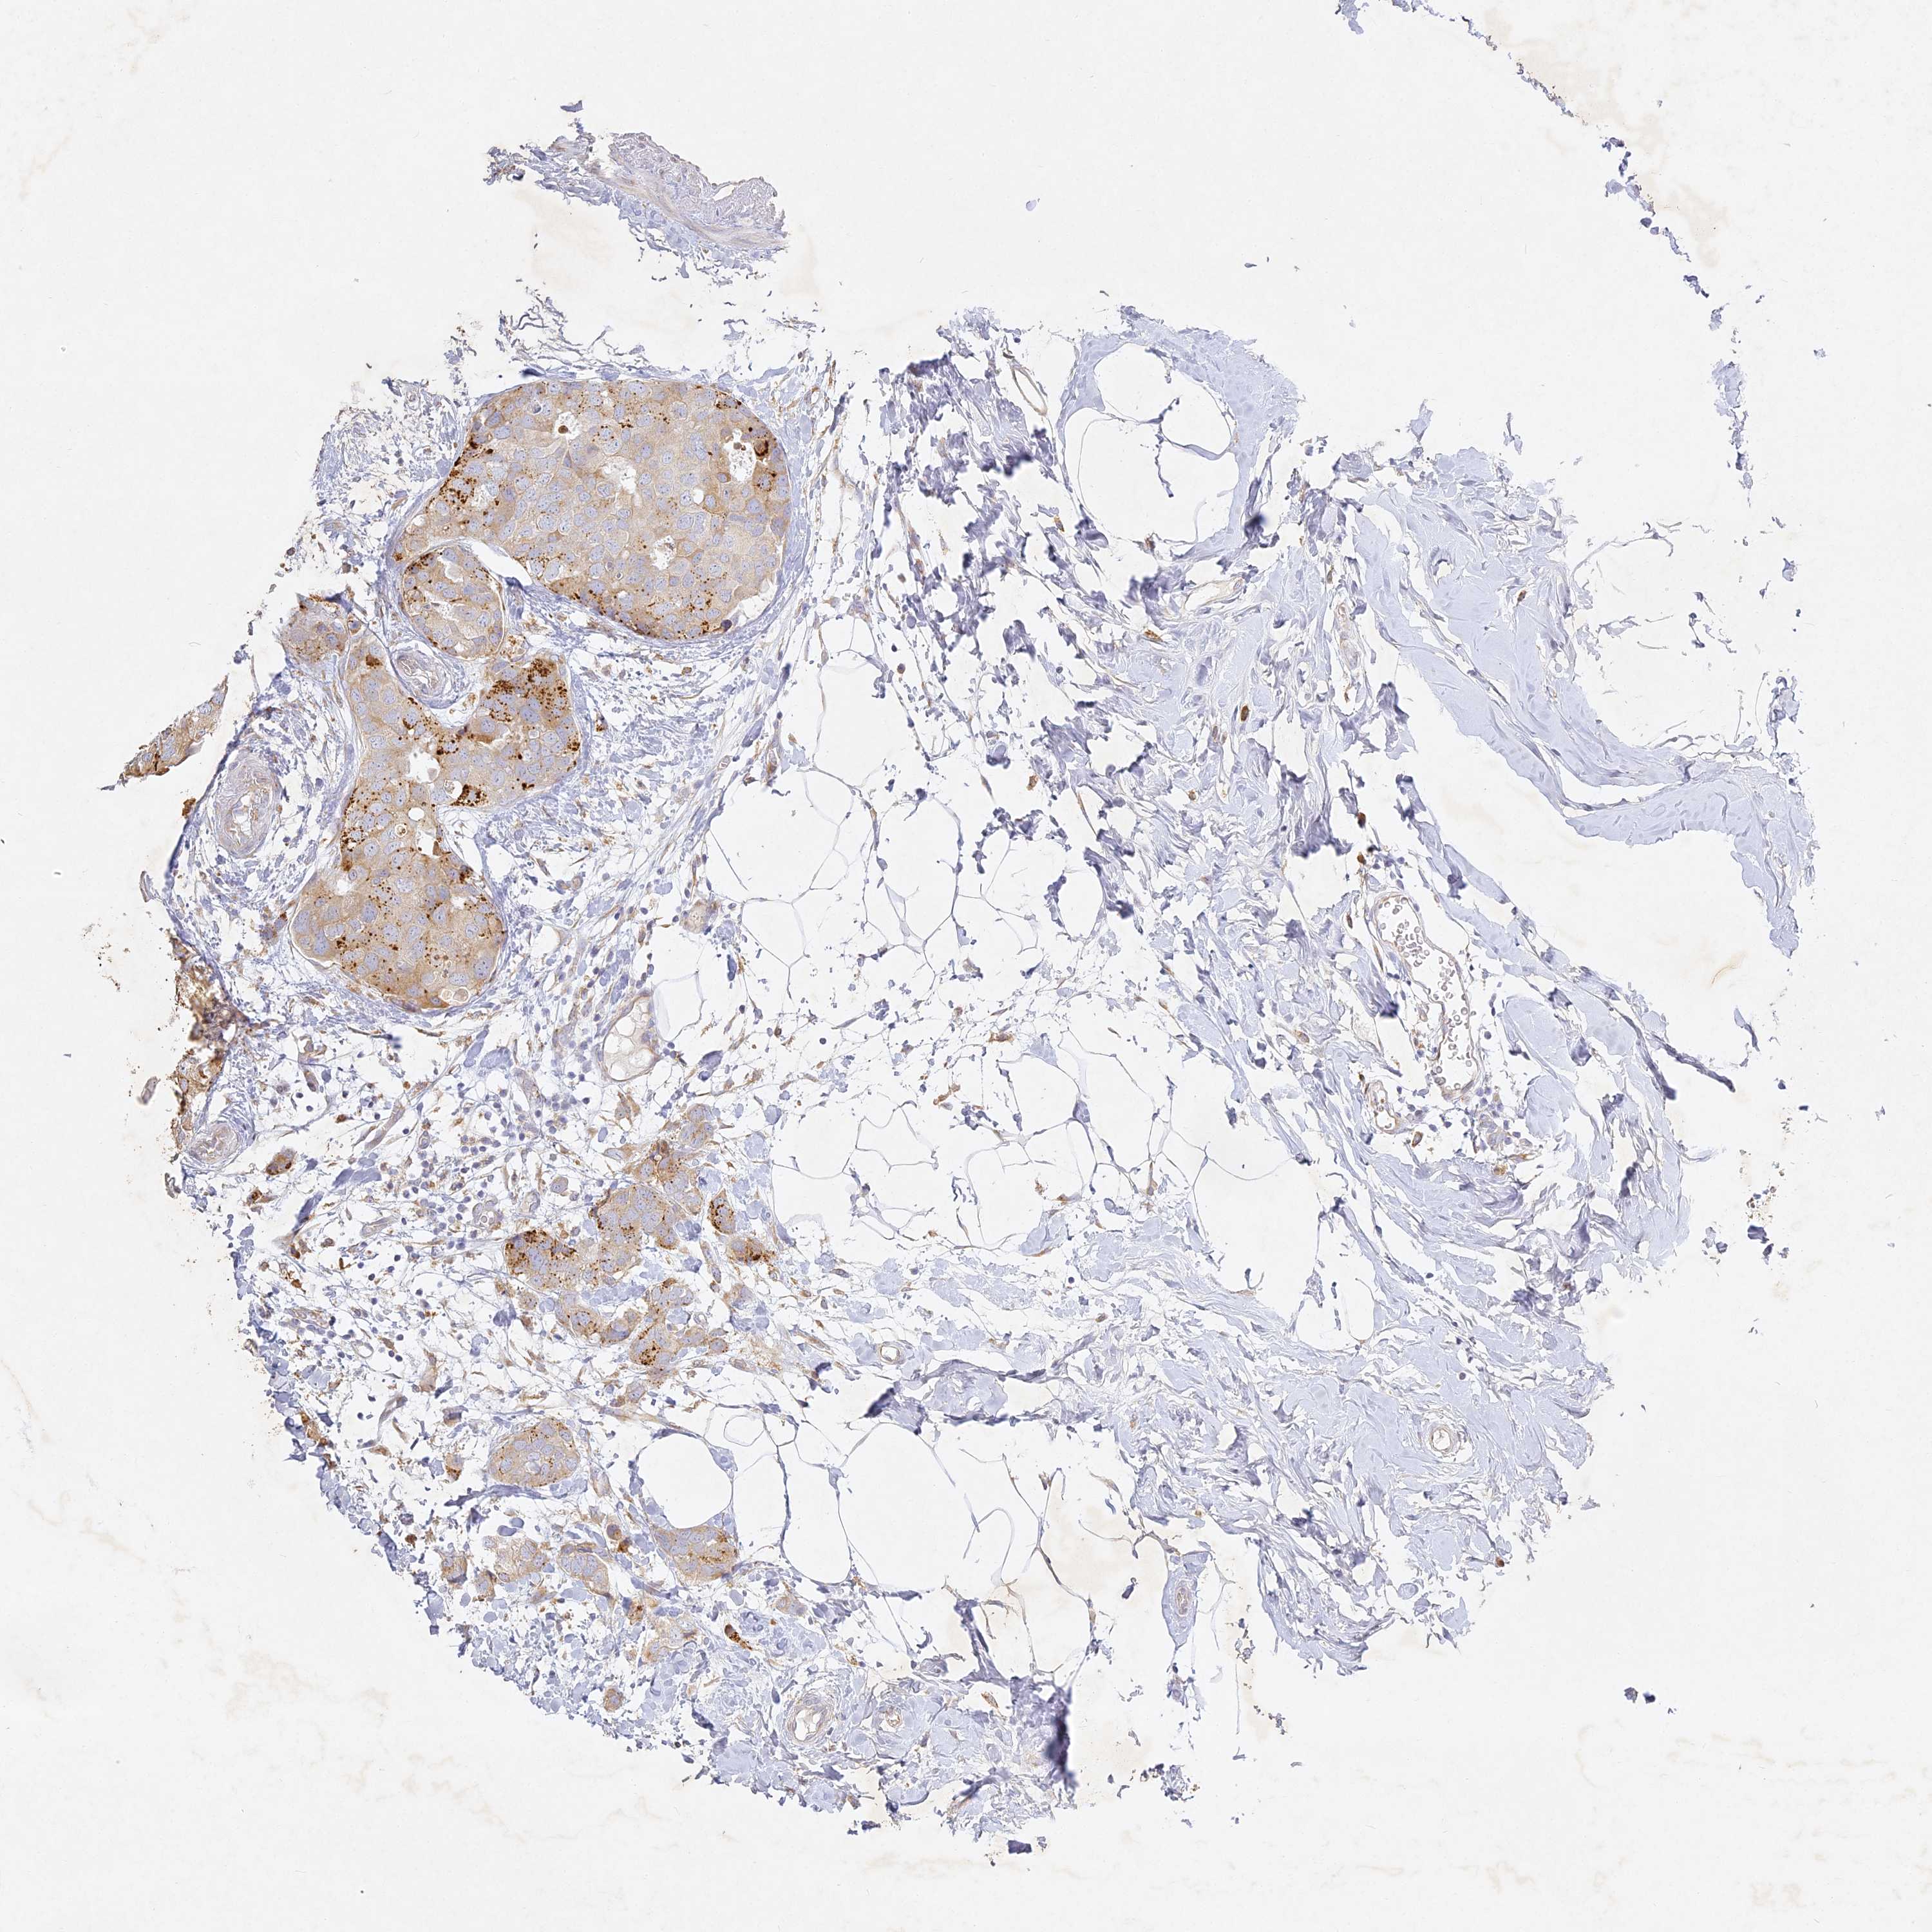

CANCER BREAST CANCER Show tissue menu

BRCA TCGA BRCA VALIDATION PROTEIN EXPRESSION